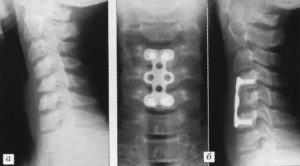

- Динамическая фиксация. Данная техника протезирования способствует стабилизации позвонков, при которой сохраняется незначительная подвижность позвонков. Чаще всего имплантат, в качестве которого преимущественно применяются титановые пластины, вживляется между остистыми отростками в пояснично-крестцовом отделе. Такая операция обычно проводится при стенозе, радикулопатии, грыже или смещении позвонков назад.

- Транспедикулярная стабилизация. С помощью специальной ножки (педикулы) в смежные позвоночные тела вставляется корригирующая металлическая конструкция в виде винтов, крепко соединенных между собой штангами. Подобная техника чаще всего применяется при смещении или переломе позвонков.

Техника стабилизации поврежденных позвонков подбирается специалистом в индивидуальном порядке, учитывая множество факторов: тип повреждения, возраст и состояние здоровья пациента, наличие противопоказаний. Для операции могут применяться различные металлоконструкции: винты, пластины, стержни, скобы.